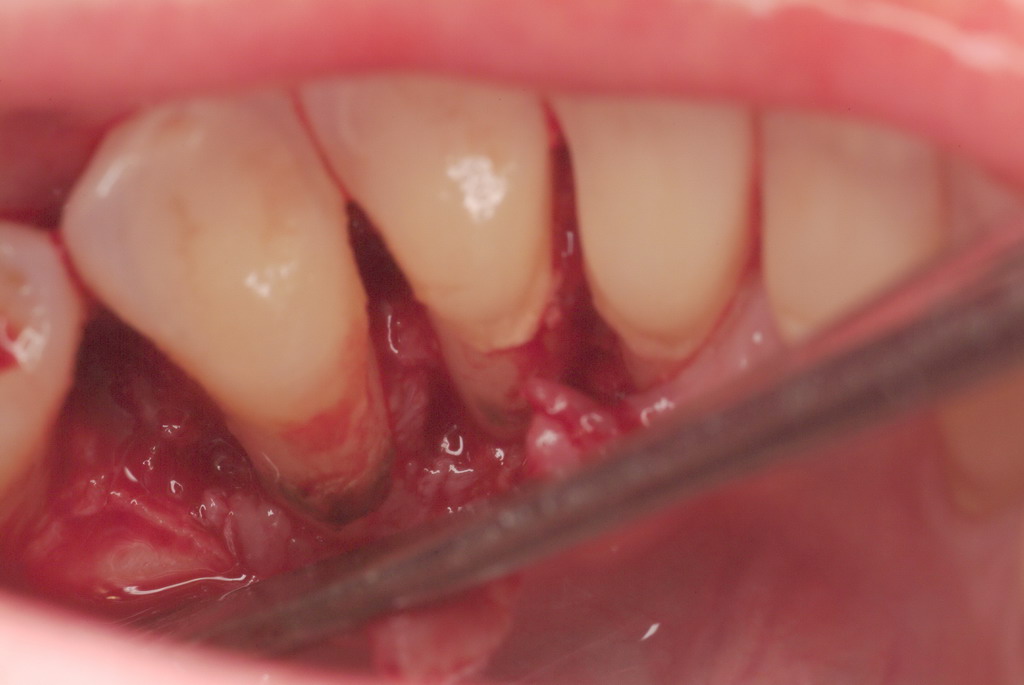

The patient had been referred for an implant consultation for the mandibular right canine. She had very deep probing depths on the lingual. When the flap was raised, a significant amount of subgingival calculus was seen as a local risk factor (Figure 18). However, she had no significant pathology to remove from the situation. Debridement was performed the same as in Case 3 with the rotary ultrasonic and manual instrumentation.

Subgingival calculus and severe bone loss.

Figure 18